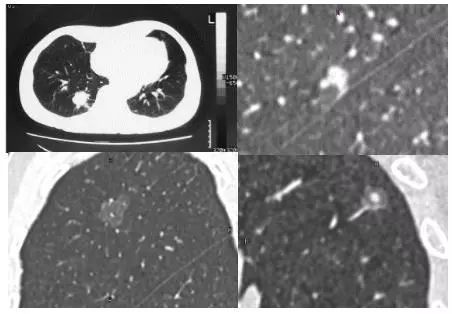

实性肺结节(solid nodule),间质血管都看不见(左上图),亚实性肺结节(subsolid nodule)包括纯磨玻璃结节(pure ground-class nodule,pGGN)(左下图),还有混杂性结节(mixed ground-glass nodule,mGGN),也称部分实性结节(part solid nodule),表现为间质样改变,中间实性,周围是磨玻璃样。